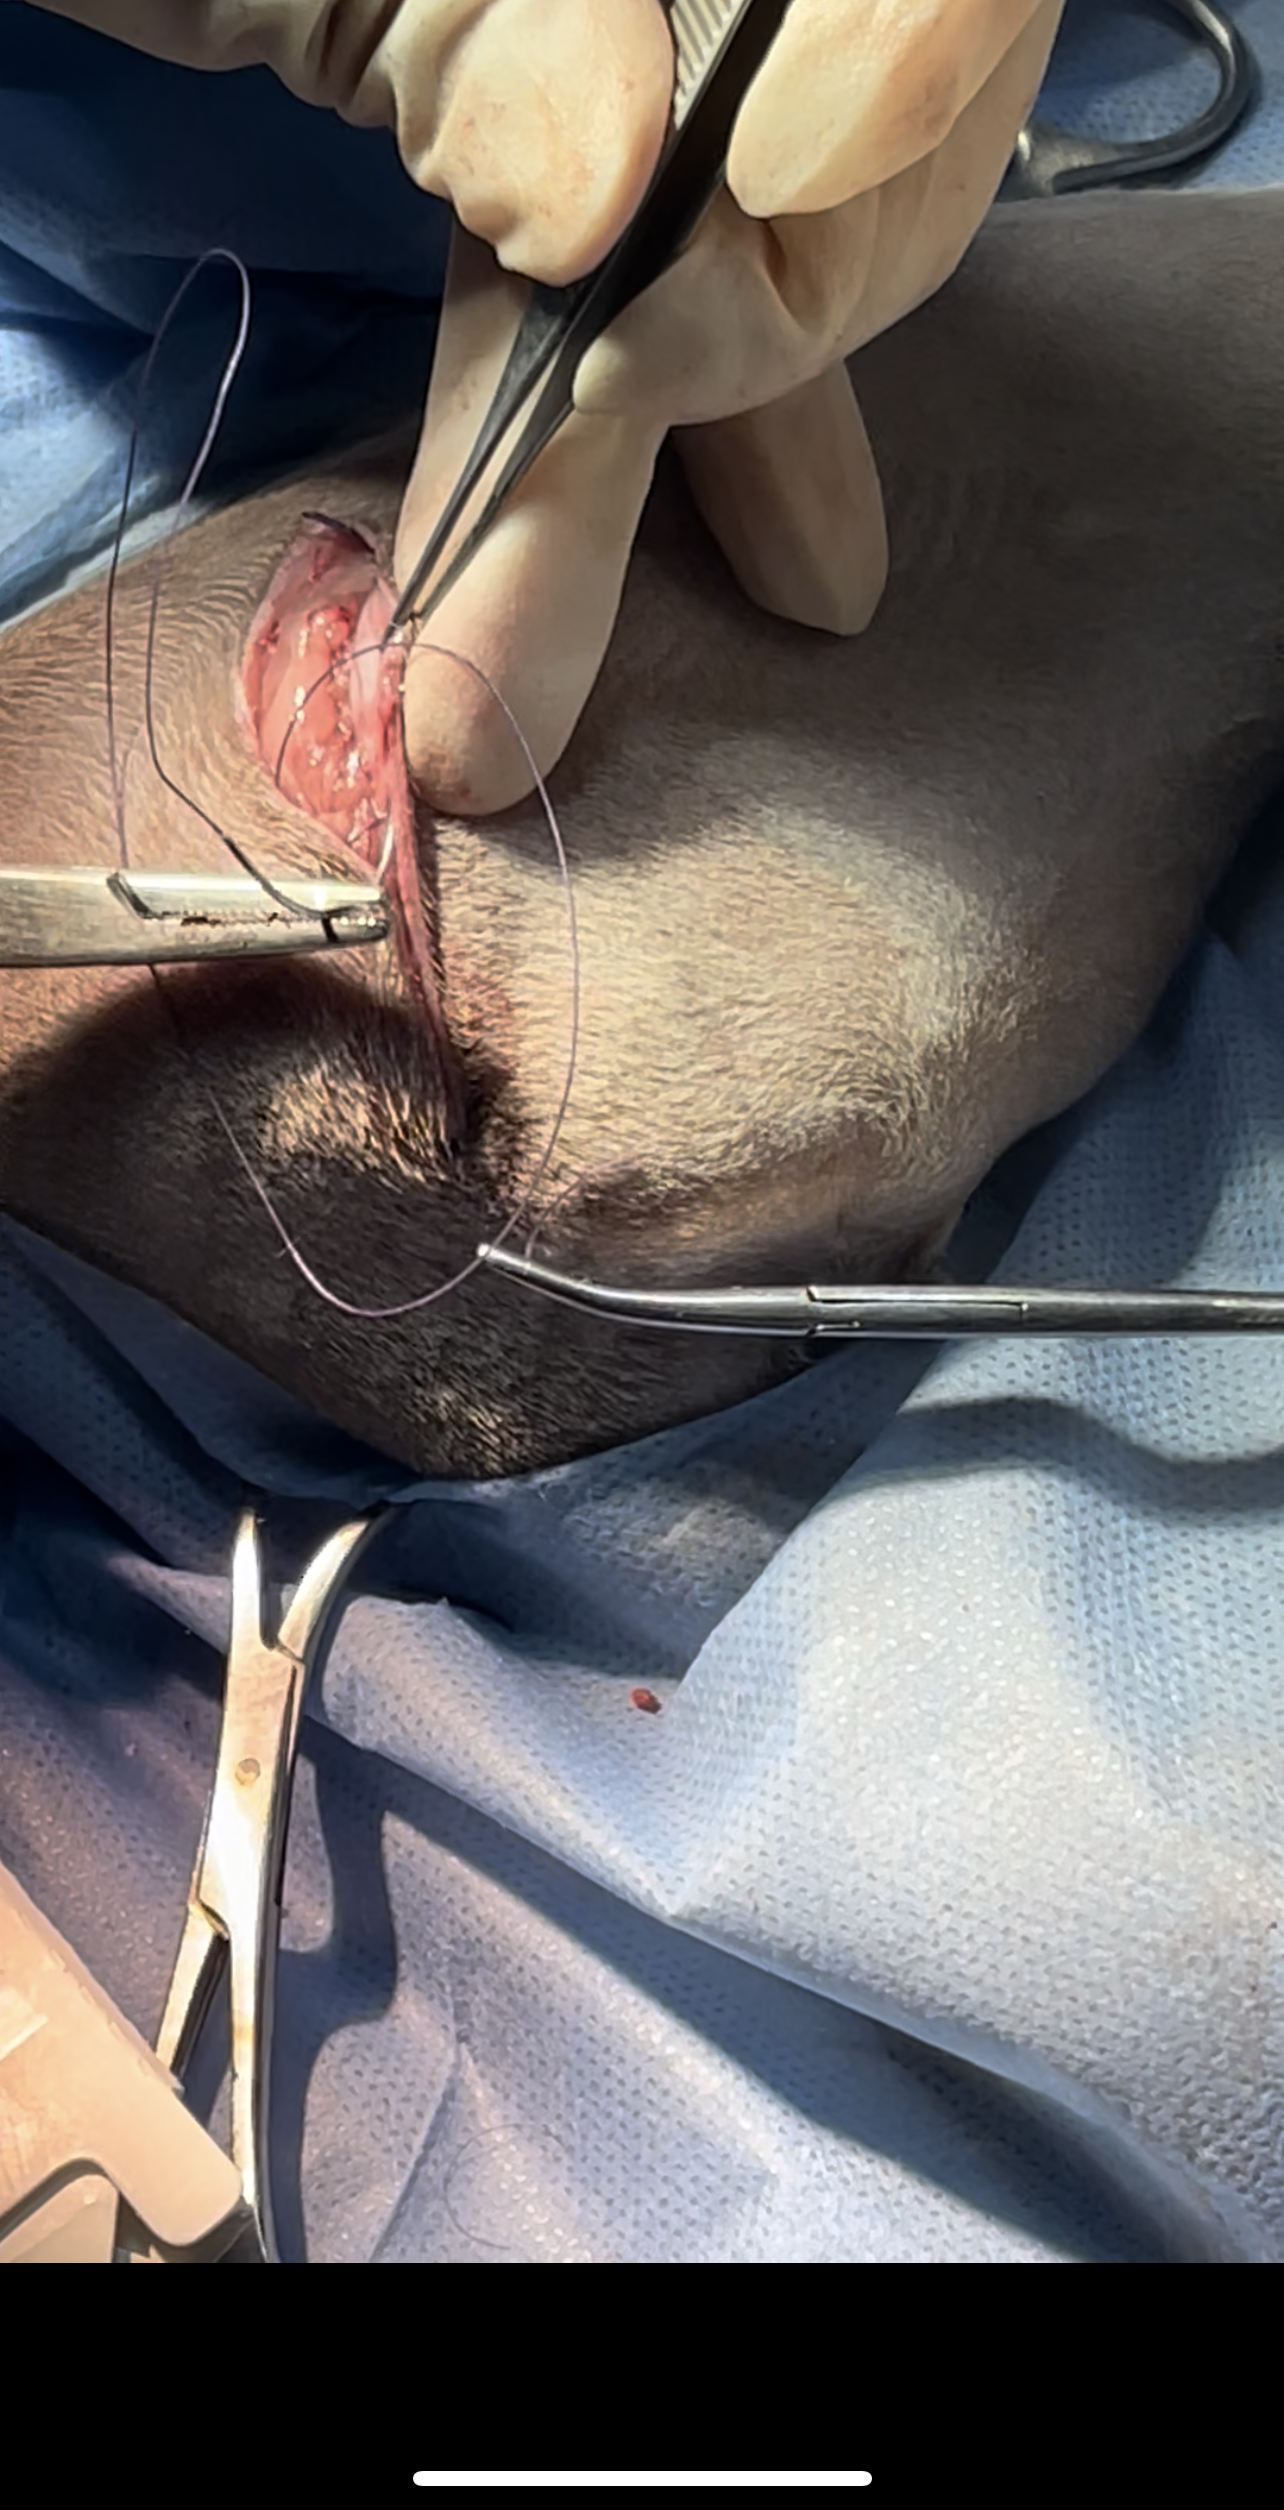

Femoral Head and Neck Ostectomy (FHO) is a salvage surgical procedure performed to eliminate pain and restore functional limb use in animals suffering from severe hip joint

disease

The surgery involves removing the femoral head and neck, thereby eliminating bone-to-bone contact and allowing a fibrous pseudoarthrosis (“false joint”) to form

Bilateral FHO was recommended starting with the right most affected limb and the other to be scheduled after 2 months